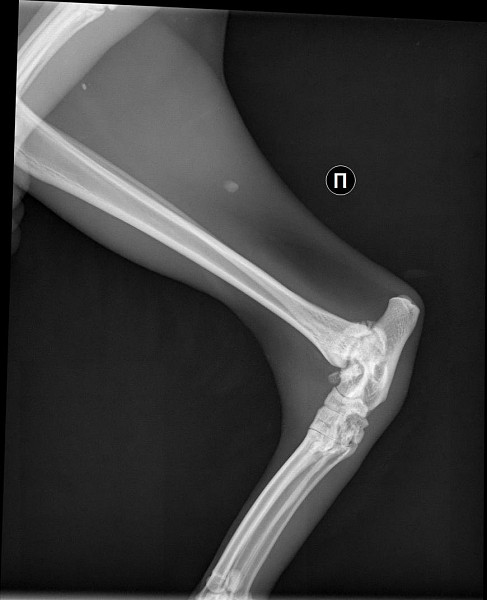

Рентген Задней Лапы Кошки: Нормы и Диагностика